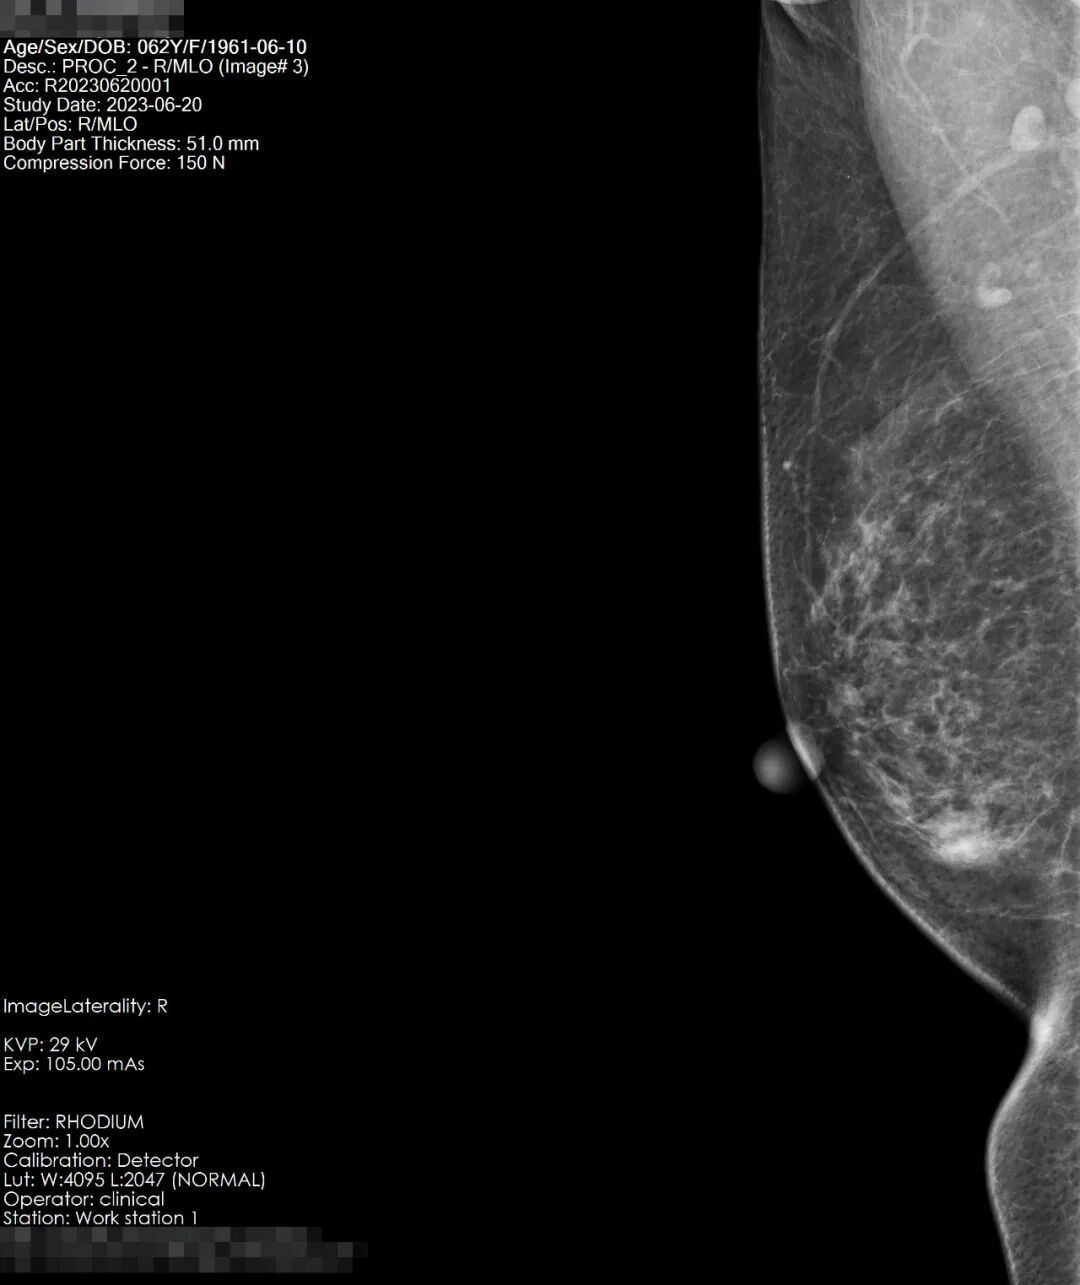

患者吴女士,58岁,在偶然一次洗澡发现自己右乳的乳头发硬并有变大的趋势,于是在网上找到了“自检”的小科普,对着镜子,开始自检,触及有疼痛感,遂即至宏宇浣江医院放射科,行乳腺钼靶检查。

检查所见:双乳腺呈散在纤维腺体型,乳腺组织丰富呈斑片状密度影,右乳内下像限见一密度增高结节影,大小约14*11mm左右,略呈分叶状,边界尚清,未见毛刺及成簇细小钙化。左乳未见明显异常,双侧腋下小淋巴结显示。双乳皮肤光整,皮下组织结构清晰,双乳头无殊。

结果显示:右乳内下像限结节,建议穿刺活检,(BI-RADS-Ⅳb类)。双侧腋下小淋巴结显示。

患者于8月2日至杭州邵逸夫医院进行全麻手术,术后病理结果为乳腺浸润性癌I期<早期>。